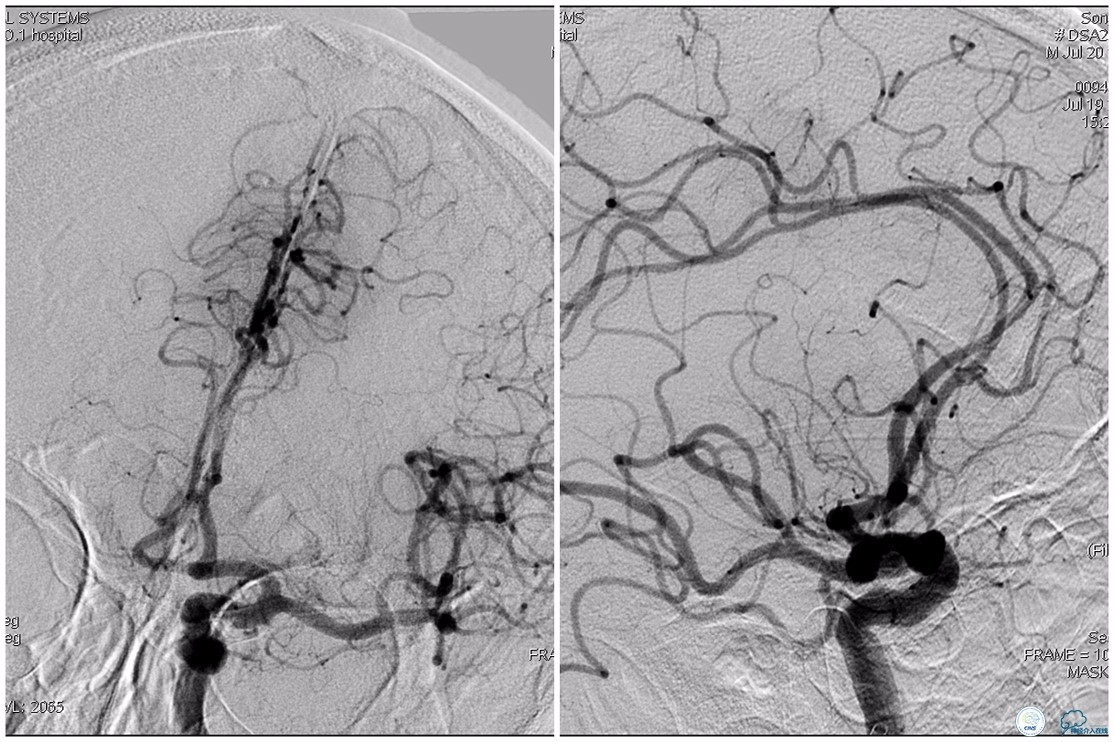

12:35穿刺成功,TOT 185min。3型主动脉弓,右侧颈内动脉起始部狭窄70%,右侧大脑前动脉A1段未显影。

双侧大脑前动脉A4段闭塞,右侧大脑前动脉由左侧大脑前动脉经前交通动脉代偿供血。

双侧大脑前动脉完全显影,TICI 3级,TOR 261min。